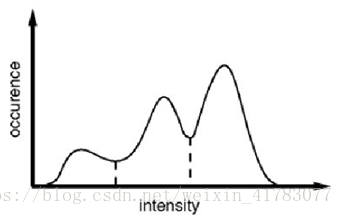

图像阈值分割是一种广泛应用的分割技术,利用图像中要提取的目标区域与其背景在灰度特性上的差异,把图像看作具有不同灰度级的两类区域(目标区域和背景区域)的组合,选取一个比较合理的阈值,以确定图像中每个像素点应该属于目标区域还是背景区域,从而产生相应的二值图像。阈值分割法的特点是:适用于目标与背景灰度有较强对比的情况,重要的是背景或物体的灰度比较单一,而且总可以得到封闭且连通区域的边界。图1中显示了图像灰度直方图中潜在的两个分界点,如图中虚线所示。如果需要在阈值法的过程中寻找不止一个的阈值来对图像的像素点进行分类,那么这种方法叫做多阈值法。

图1 图像灰度上确定阈值示例

阈值法在实际应用中主要存在两个问题:(1)该方法只考虑到图像中像素点本身的灰度值,没有考虑到图像中像素点的空间分布,容易对噪声敏感。(2)该方法对于背景与目标区域灰度差异较小的图像分割效果不好。医学图像因个体差异而复杂多样,如:不均匀的人体组织器官常导致图像灰度不均匀;人体组织的蠕动及成像设备的局限性常导致图像中存在伪影和噪声;局部体效应常导致组织边缘模糊;病变组织的病变边缘不明确等。阈值法在医学图像分割中具有一定的局限性。